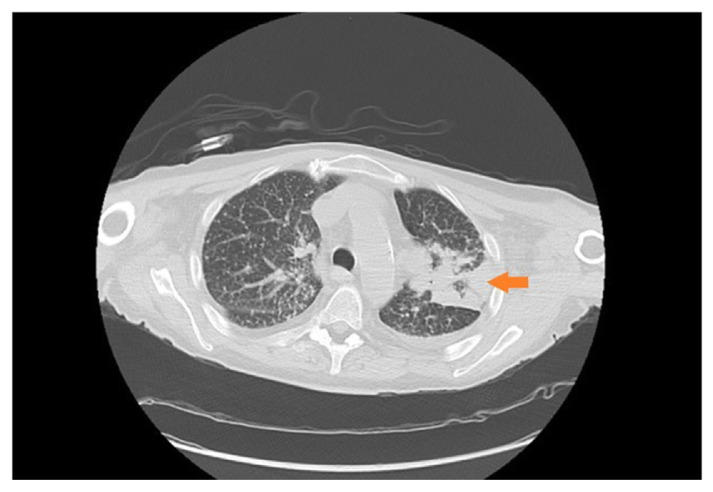

Case report: A 67-year-old patient with history of tobacco use, atrial fibrillation, type 2 diabetes, hyperlipidemia, and bilateral deceased donor kidney transplantation (DDKT) in 2021, presented to Charleston Area Medical Center's (CAMC), Charleston WV, Emergency Department (ED) for fever and night sweats. Initial workup revealed 39.4 °C temperature with remaining vital signs normal. Corona, parainfluenza, influenza, metapneumovirus, mycoplasma pneumonia, RSV were negative, GI PCR panel was negative for C. difficle, yersinia, campylobacter, giardia, vibrio, norovirus, salmonella, rotavirus. Chest X-ray showed a 2.1 × 1.6 cm nodular density in the left upper lobe (LUL) lobe. White blood cell (WBC) count was elevated at 13000/mcl with a left-sided shift. Subsequent computed tomography (CT) of the chest without contrast demonstrated a 2.7 × 2.1 cm LUL mass. Urine Blastomyces antigen tested positive, prompting the initiation of empiric therapy for blastomycosis. Aspergillus was ruled out initially.